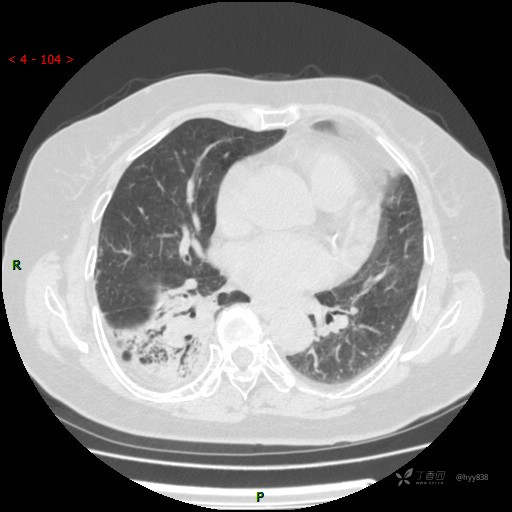

静脉期